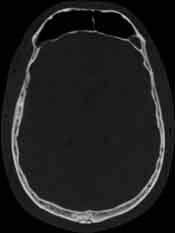

Visible Human male: Sectio transversalis 1080

CT

NMR

Pd T1 T2